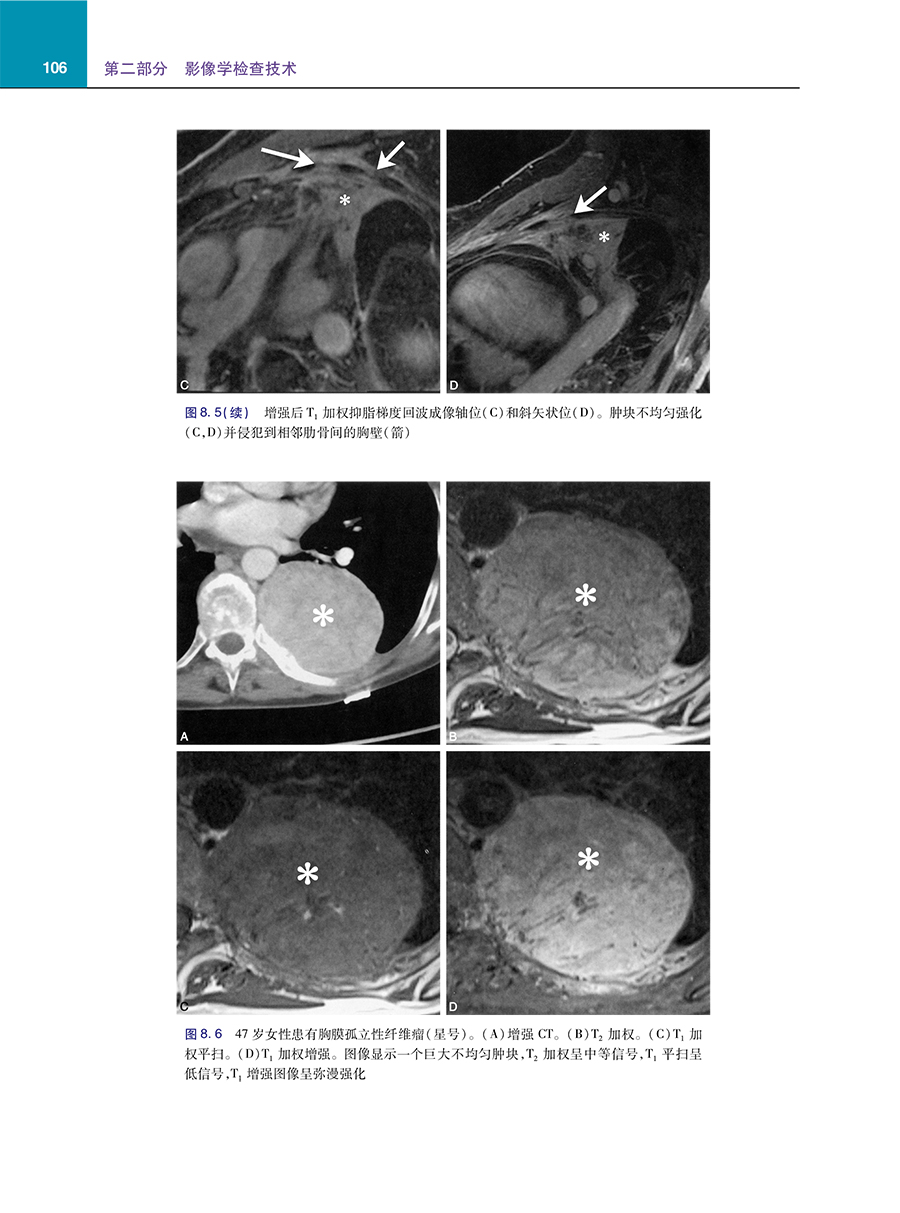

4 呈现1,500多张高质量图像,可清晰地阐释问题解析的内容。

5 专注于胸部影像问题解析所需的核心知识,包括解剖学、成像技术、成像方法、按病理和解剖区域以及特殊情况划分的病种。

主要主题包括弥漫性肺病、肺和气道肿瘤、间质性肺病、吸烟相关肺部疾病和心血管疾病。